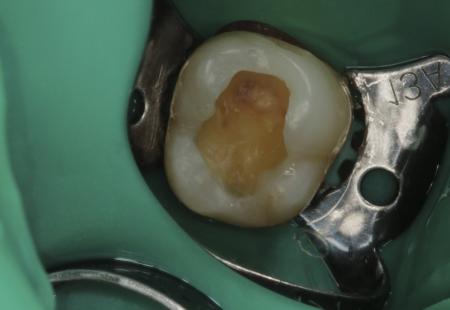

1 приём: препарирование кариозных тканей зуба, оценка потери объёма твёрдых тканей зуба и формирование полости под керамическую накладку + определение цвета зуба по шкале vita

Было проведено лечение кариеса фиссур и реставрация.